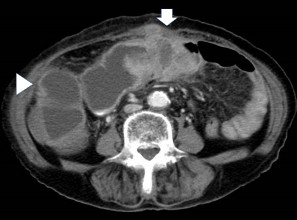

図1. 大腸閉塞の腹部CT検査

横行結腸の腫瘍により内腔が閉塞しており(矢印)、

口側大腸の拡張を認める(矢頭)。

腹部レントゲン検査および腹部CT検査によって閉塞部位を同定します。また同時に、消化管閉塞の部位が複数ないことを確認します。その後、消化管造影検査や内視鏡検査によって実際の消化管閉塞の詳細を評価します。